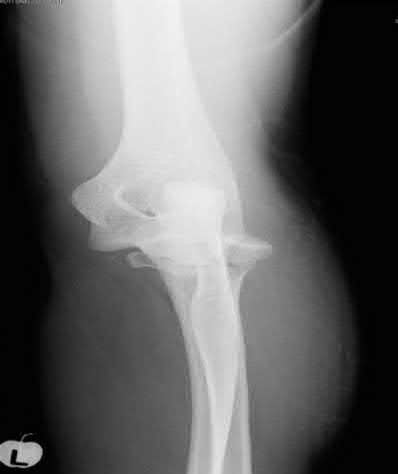

Question 3:

A 15-year-old boy presents with a permeative lytic lesion in the femoral diaphysis with aggressive periosteal reaction ('onion skinning'). Biopsy reveals uniform small round blue cells. Cytogenetic analysis of this tumor will most likely demonstrate which of the following translocations?

Options:

- t(11;22)

- t(9;22)

- t(2;13)

- t(X;18)

- t(12;16)

Correct Answer: t(11;22)

Explanation:

The clinical and radiographic description is classic for Ewing sarcoma. The characteristic cytogenetic abnormality is a balanced translocation t(11;22)(q24;q12), which fuses the EWS gene on chromosome 22 with the FLI1 gene on chromosome 11. This is seen in approximately 85-90% of Ewing sarcomas. t(9;22) is the Philadelphia chromosome (CML), t(X;18) is seen in synovial sarcoma, t(2;13) in alveolar rhabdomyosarcoma, and t(12;16) in myxoid liposarcoma.